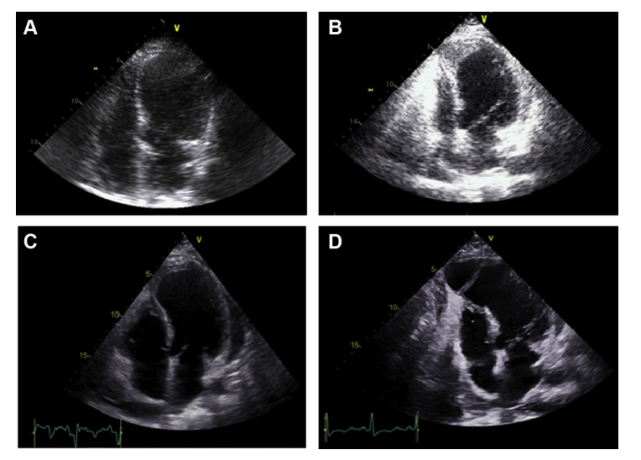

室早二连律

3月22日,超声心动图:左心房前后径41mm,左心室舒张末期内径54mm,左